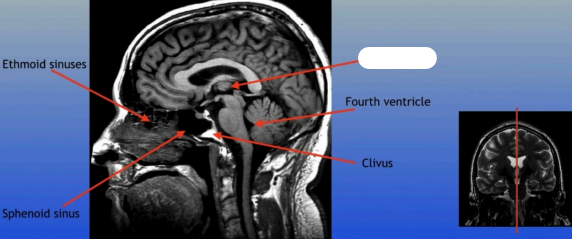

Ethmoid Sinuses

Sphenoid Sinus

Fourth Ventricle

Clivus

Sphenoid Sinus